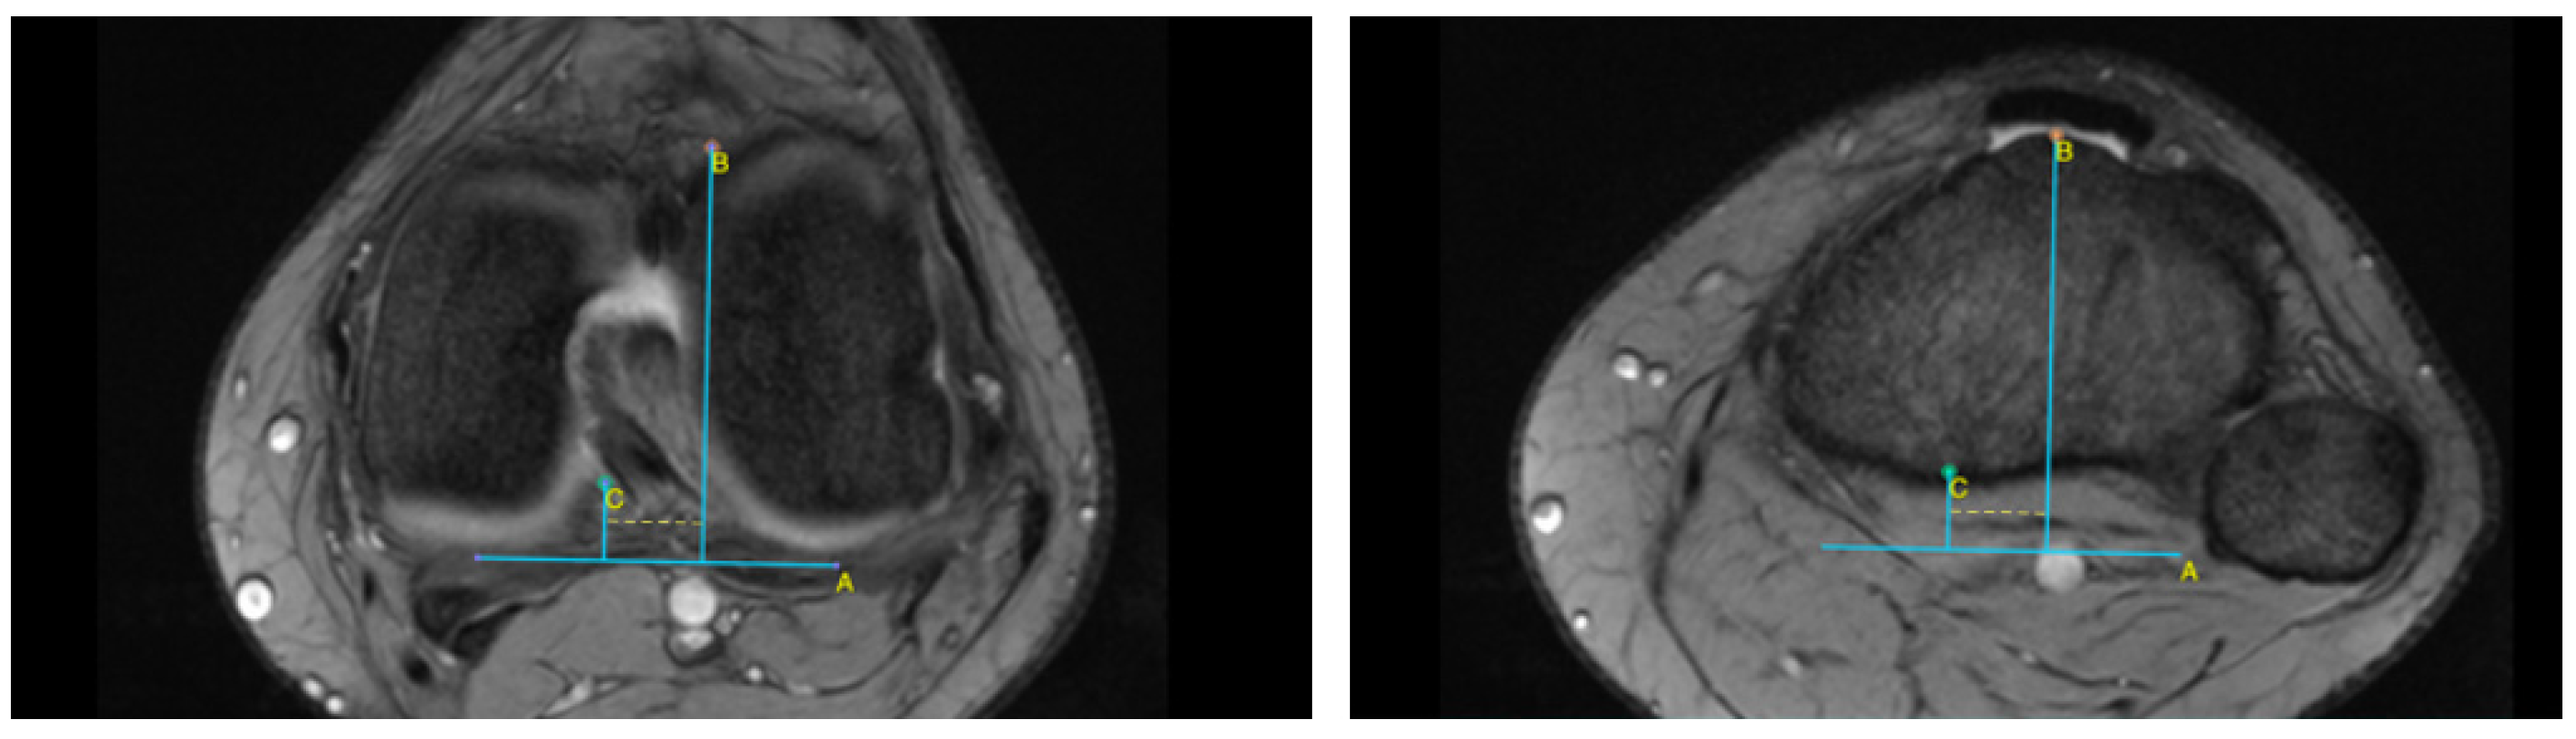

2.2. MRI Analysis